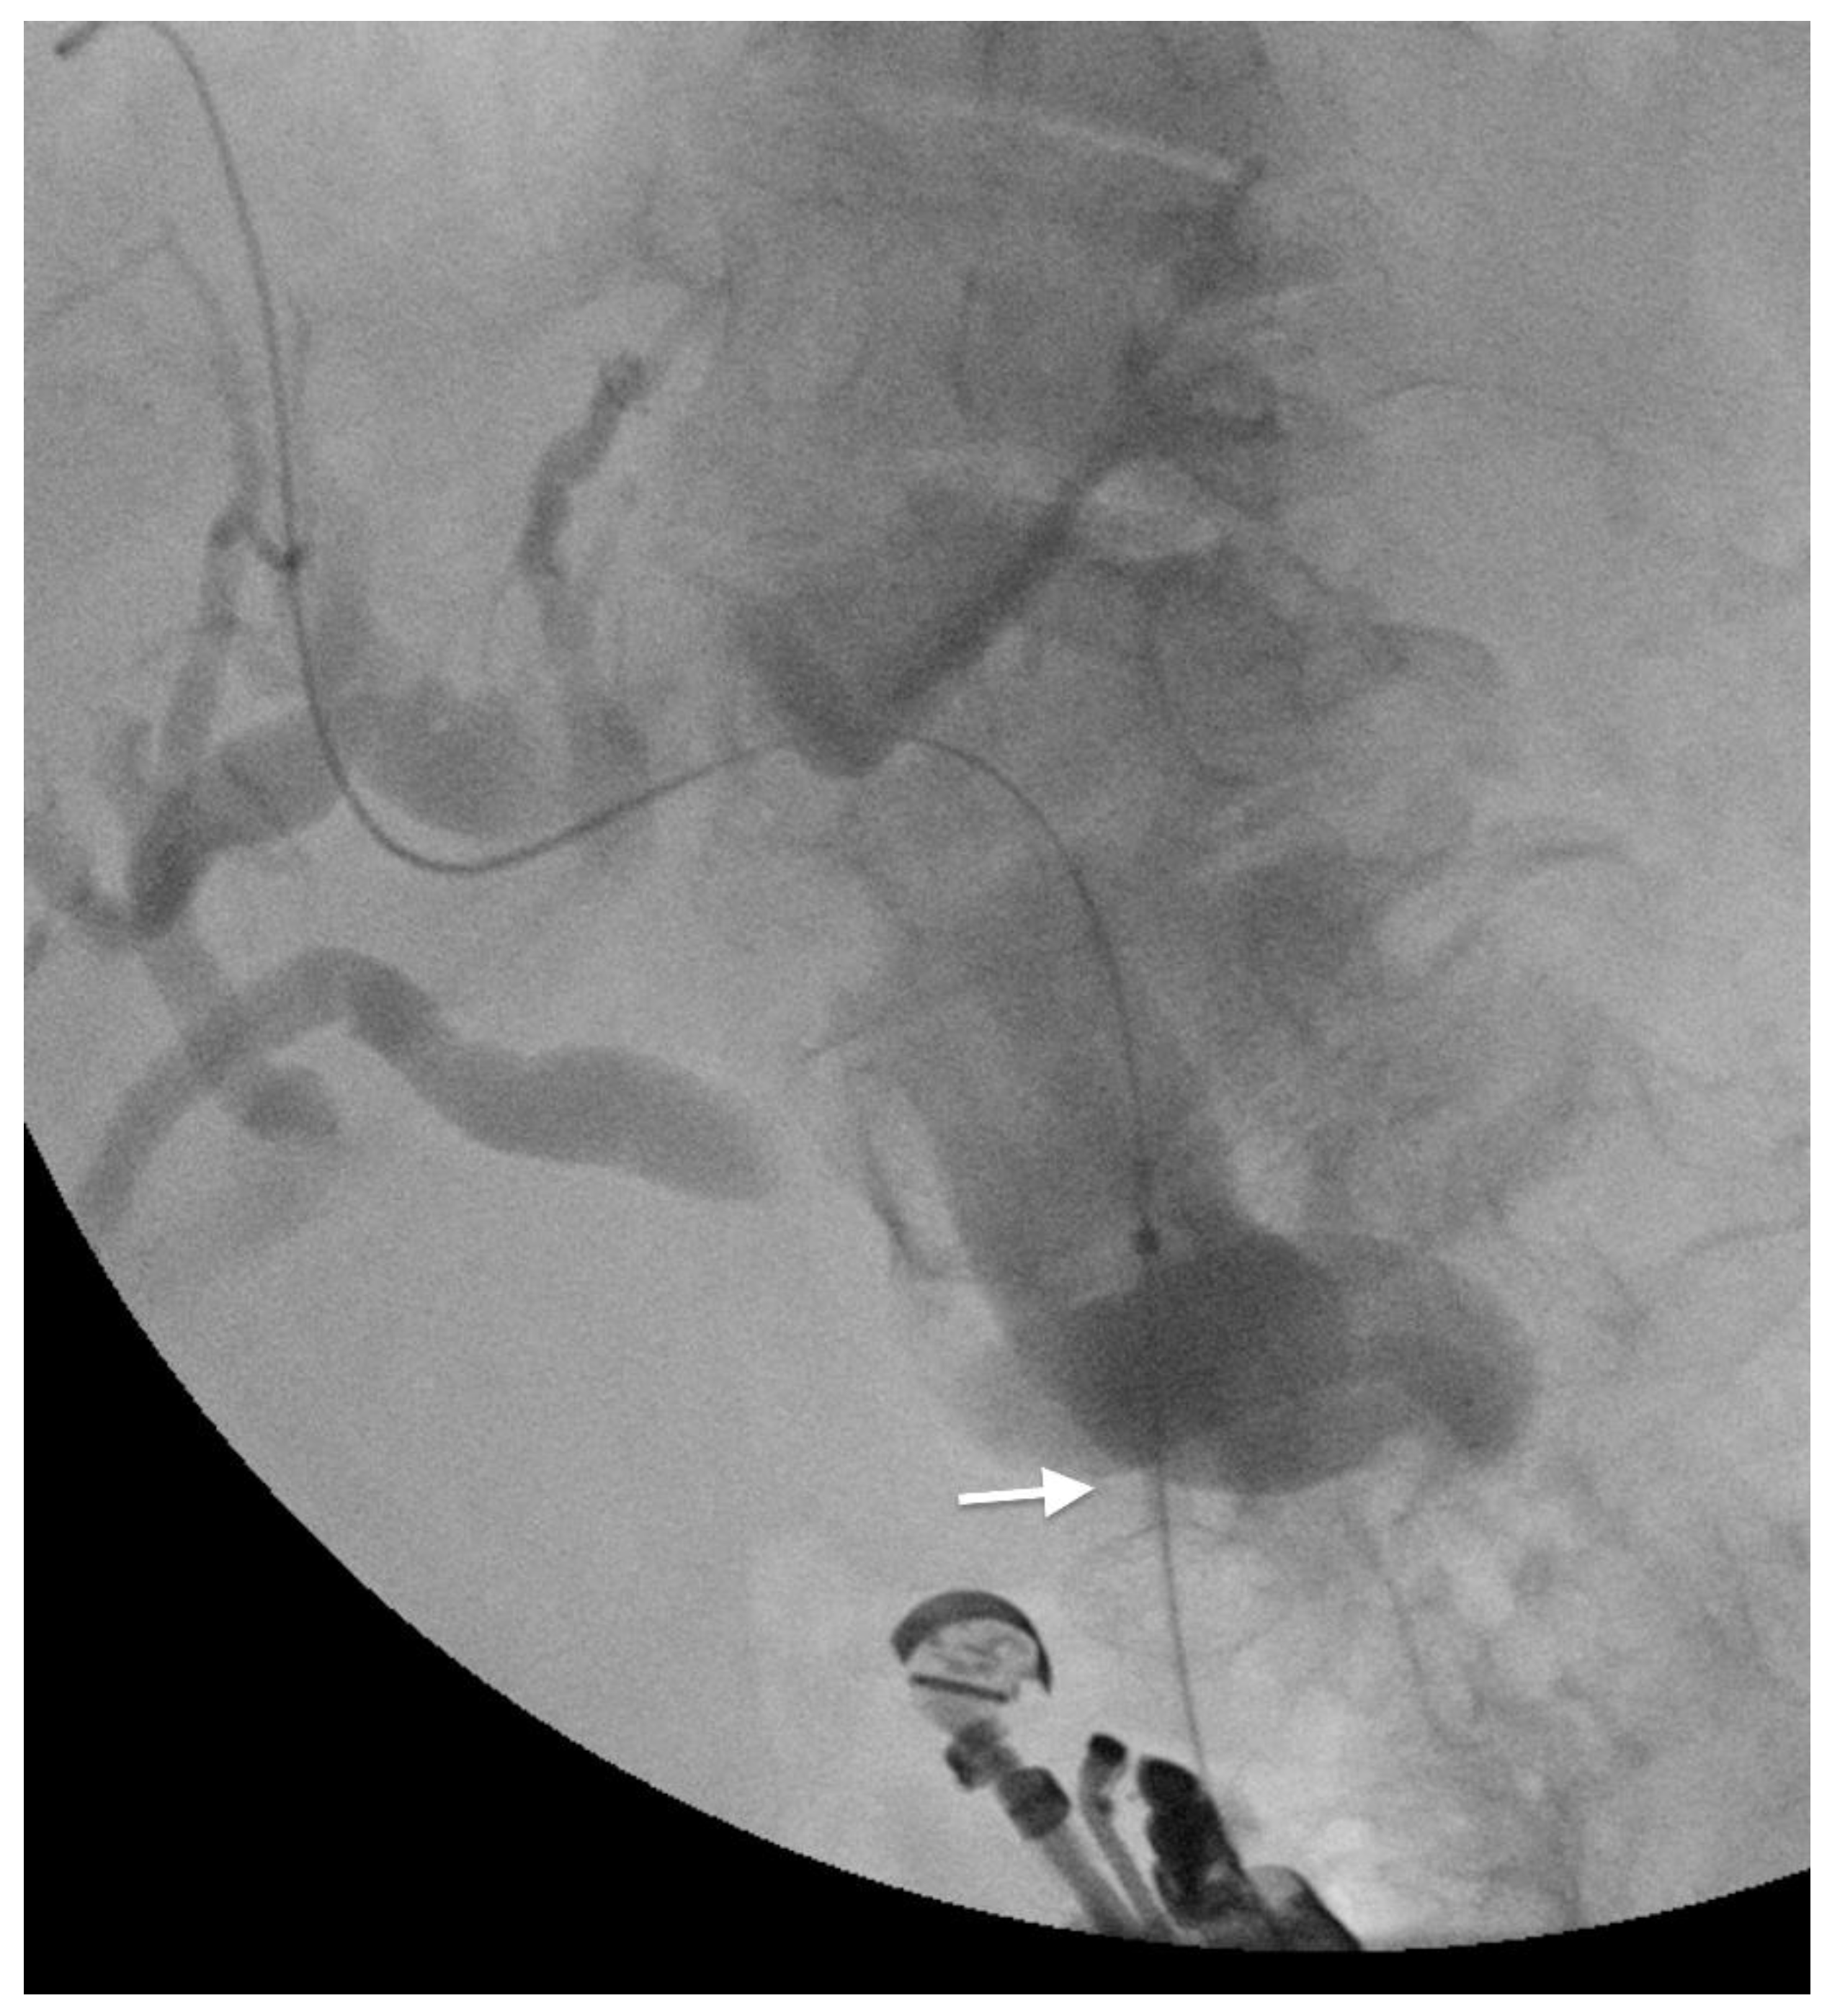

3.2. EUS-Guided Gastro-Enteral Anastomosis

- Iqbal, U.; Khara, H.S.; Hu, Y.; Kumar, V.; Tufail, K.; Confer, B.; Diehl, D.L. EUS-guided gastroenterostomy for the management of gastric outlet obstruction: A systematic review and meta-analysis. Endosc. Ultrasound. 2020, 9, 16–23. [Google Scholar] [CrossRef] [PubMed]

- McCarty, T.R.; Garg, R.; Thompson, C.C.; Rustagi, T. Efficacy and safety of EUS-guided gastroenterostomy for benign and malignant gastric outlet obstruction: A systematic review and meta-analysis. Endosc. Int. Open 2019, 7, E1474–E1482. [Google Scholar] [CrossRef] [PubMed]